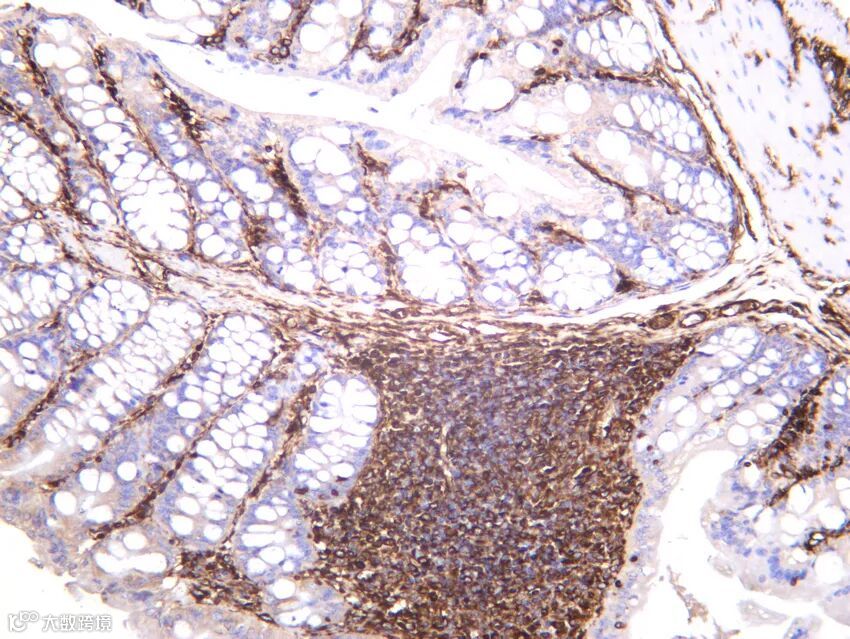

上图为混合性神经内分泌-非神经内分泌肿瘤。综合多个靶点染色分析,能更清晰区分肿瘤类型以及各肿瘤区域。(A)源于腺瘤的结肠癌,(B)常规腺癌,(C)低分化神经内分泌癌(NEC),(D)CDX2在结肠黏膜、腺瘤和腺癌中表达,但在 NEC 中几乎缺失,(E)突触素则呈现相反的模式, (F) Rb 缺失仅限于NEC。